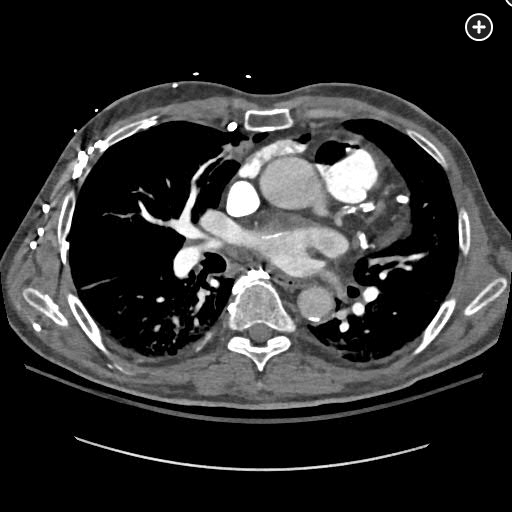

The CT pulmonary angiogram demonstrates a large volume of air in the right atrium, ventricle, and pulmonary outflow tract, with leftward bowing of the interventricular septum, suggestive of acute right heart strain (Figure 1, Figure 2, Figure 3, Figure 4).

CT image demonstrating air in the right ventricle with leftward bowing of the interventricular septum, indicative of acute right heart strain.